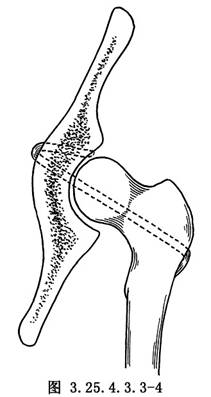

用4mm直徑斯氏針於大粗隆下緣向股骨頭中央鑽洞,將大粗隆基底帶蒂的髂脛束條縫成管狀,用有孔探針由大粗隆基底的骨洞穿入,由股骨頭中心拉出。再於髖臼中央偏前方,用骨鑽鑽洞,由髂骨內面的骨洞放入探針,將再造的圓韌帶由洞內拉出,將股骨頭復位,將圓韌帶拉緊與髖臼上緣的骨質和肌附麗再縫合固定,或於髂前下棘處鑽洞成襻狀縫合固定(圖3.25.4.3.3-3~3.25.4.3.3-6)。